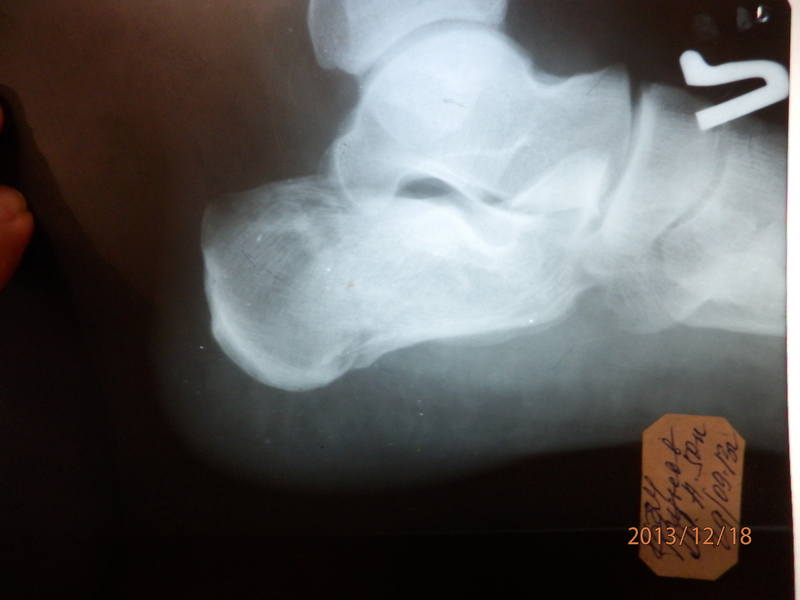

Перелом Пяточной Кости Фото💣 👉🏻👉🏻👉🏻 ИНФОРМАЦИЯ ДОСТУПНА ЗДЕСЬ! КЛИКАЙ 👈🏻👈🏻👈🏻Перелом Пяточной Кости Фото